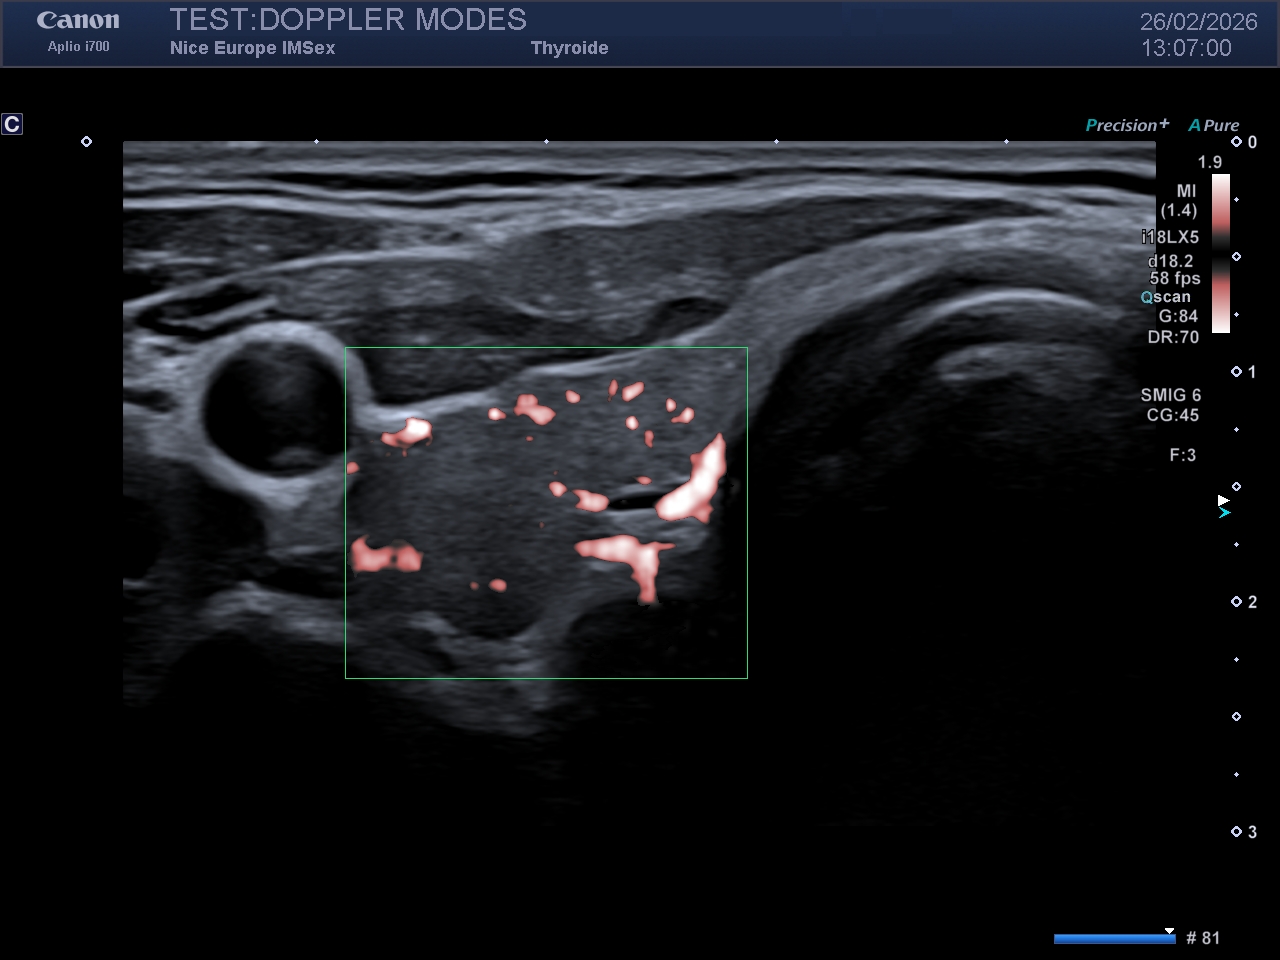

Légende : Image en Doppler couleur d'un rein droit

La détection de la microvascularisation tissulaire (flux très lents dans des vaisseaux inframillimétriques) a longtemps été entravée par le filtre de paroi (Wall Filter). En Doppler classique, ce filtre supprime les signaux de basse fréquence et de forte amplitude générés par les mouvements tissulaires physiologiques (clutter). Malheureusement, les flux sanguins microvasculaires possèdent également de très basses fréquences. Le filtre supprime donc le tissu, mais efface simultanément l'information microvasculaire.

L'apport technologique des Ondes Planes (Plane Wave Imaging) :

Les modes microvasculaires de dernière génération (déclinés selon les constructeurs sous diverses appellations telles que SMI - Superb Micro-vascular Imaging, MFI - MicroFlow Imaging, MV-Flow, Micro Angio, LumiFlow, etc.) contournent ce problème grâce à l'imagerie ultrarapide. Au lieu d'émettre des faisceaux focalisés ligne par ligne, la sonde émet des "ondes planes" non focalisées balayant l'ensemble de la zone en une seule émission. Cette technique permet d'acquérir des milliers d'images par seconde.

Le traitement par Décomposition en Valeurs Singulières (SVD) :

Cette résolution temporelle extrême permet d'abandonner le filtrage fréquentiel classique au profit d'un filtrage spatio-temporel avancé, basé sur la Décomposition en Valeurs Singulières (SVD). La SVD sépare les signaux selon leur cohérence spatiale et temporelle : le mouvement des tissus (cohérent) est mathématiquement dissocié du mouvement des hématies dans les capillaires (incohérent).

Impact Clinique :

Le résultat est une cartographie microvasculaire d'une résolution spatiale inouïe, limitant drastiquement les artefacts de débordement (blooming artifact). Ce mode excelle dans la caractérisation fine de l'angiogenèse tumorale ou l'évaluation de l'activité inflammatoire tissulaire.